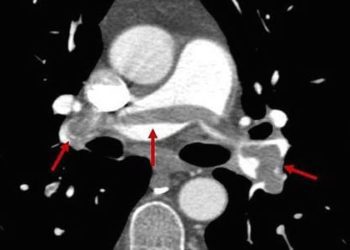

Vena cava filters plus anticoagulation do not prevent recurrent pulmonary embolism over anticoagulation alone

1. Placement of an inferior vena cava filter plus anticoagulation in high-risk hospitalized patients with acute pulmonary embolism did not ...